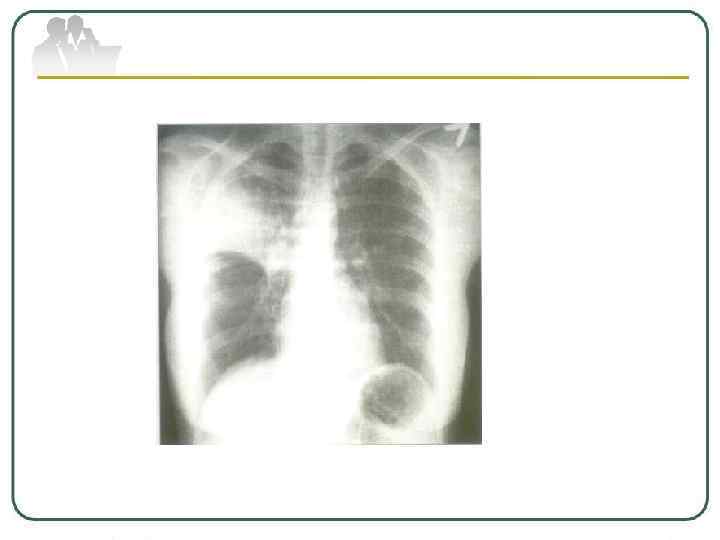

Первичный туберкулезный комплекс характеризуется развитием воспалительных изменений в легочной ткани, поражением регионарных внутригрудных лимфатических узлов и лимфангитом. Он преимущественно наблюдается в детском возрасте. Клинические проявления первичного комплекса зависят от фазы процесса, особенностей течения и реактивности организма. Он может протекать малосимптомно, но чаще имеют место признаки туберкулезной интоксикации.